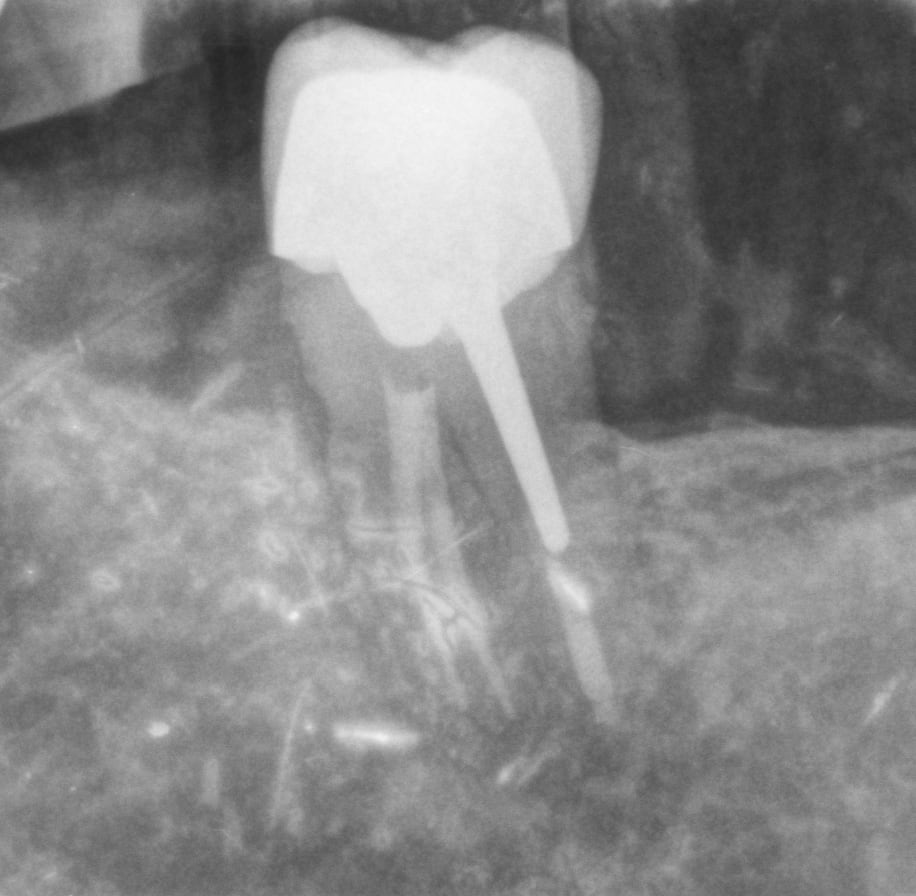

Eh sûrement, tu me connais, la radio de l endo date de 2017 , et ce matin je l ai revu pour sa radio de contrôle , dès que je fini la sieste je l envoie .

la radio de ce matin , pourrie comme toutes mes radios , mais la dent est tjs là .

1vmmitus6o1zh8rhn5rls7s9aa59 - Eugenol

Bravo,